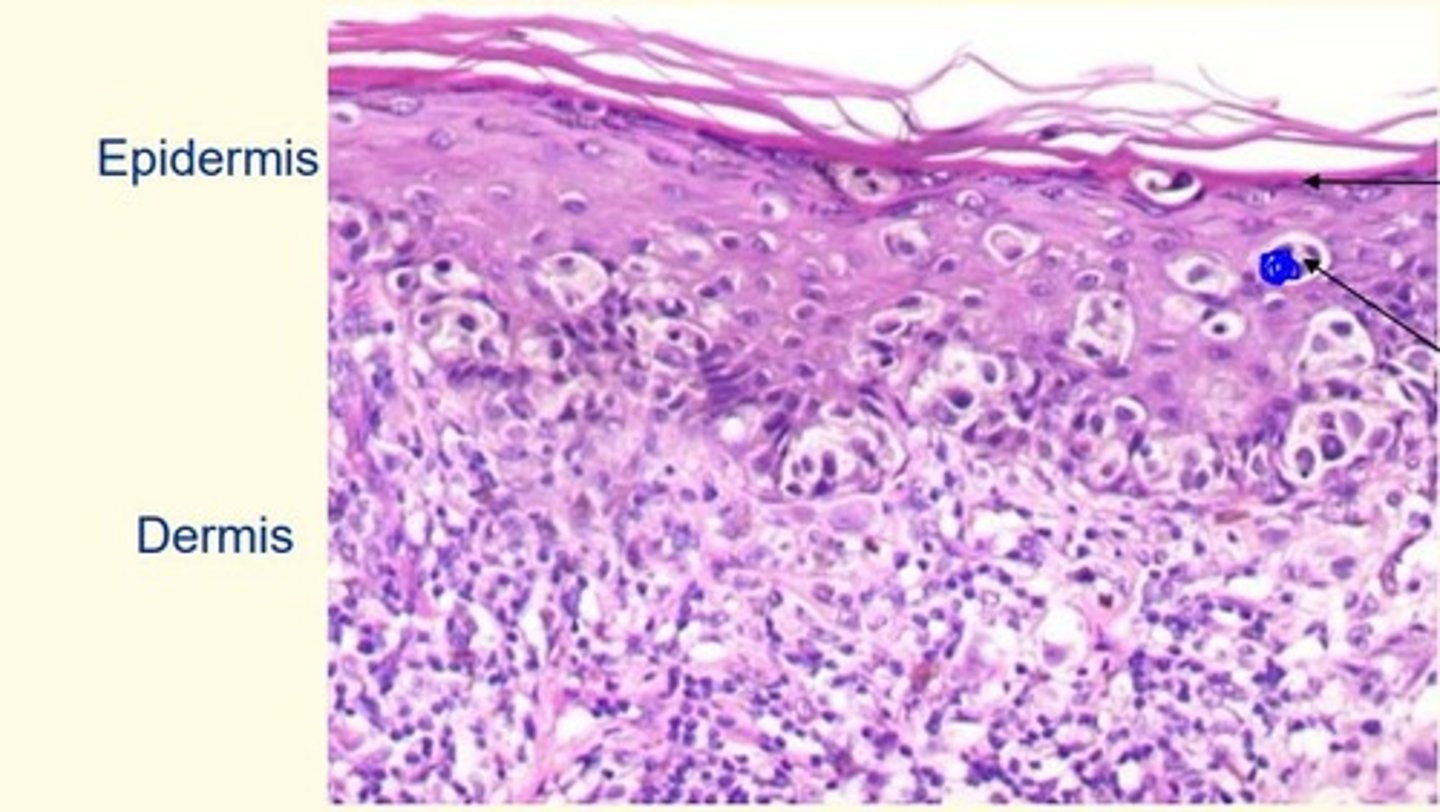

What is the arrow pointing to here. Are these cells dividing? What types of cells are they?

Dividing melanocytes

The top layer is the = granular layer (last living layer of the epidermis)

Breslow thickness

Depth of invasion of melanoma from the granular layer of the epidermis, the best predictor of 5-year survival rates